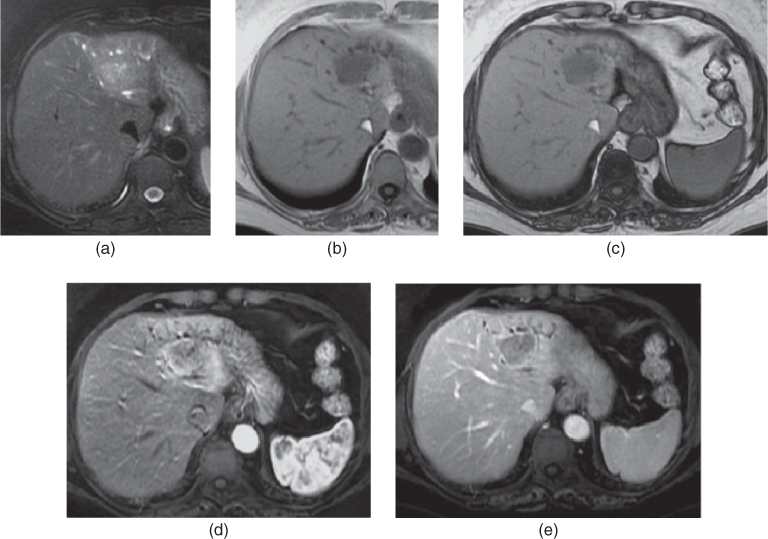

From radiologykey.com

Liver Metastases Radiology Key Endoscopic Ultrasound Liver Metastasis Overall, eus results were in accordance (moderate agreement) with ct or mri results for focal and metastatic liver lesions, with p < 0.001. Endoscopic ultrasound (eus) is an emerging imaging modality with resolution suf cient to detect. Endoscopic ultrasound (eus) is a procedure that examines your gastrointestinal tract. Liver metastases might not be detected by computed tomography (ct) and magnetic. Endoscopic Ultrasound Liver Metastasis.

From pubs.rsna.org

Liver Metastases Correlation between Imaging Features and Endoscopic Ultrasound Liver Metastasis Overall, eus results were in accordance (moderate agreement) with ct or mri results for focal and metastatic liver lesions, with p < 0.001. The use of endoscopic ultrasound (eus) examination in the diagnosis and management of gastrointestinal tumors has evolved since its inception in the 1980s. And sample lesions as small as 5. Endoscopic ultrasound (eus) is an emerging imaging. Endoscopic Ultrasound Liver Metastasis.